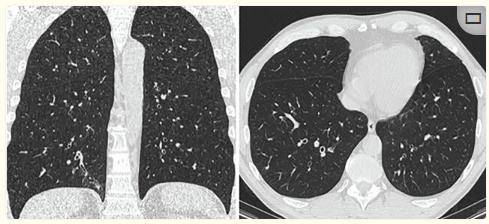

体格检查:体重指数为25 kg·m2,未被棍棒击打,胸部检查无异常。安排了进一步的检查,包括肺功能(图1和表1)、血液检查、胸部计算机断层扫描(CT)(图2)和支气管镜检查。

图2、胸部CT